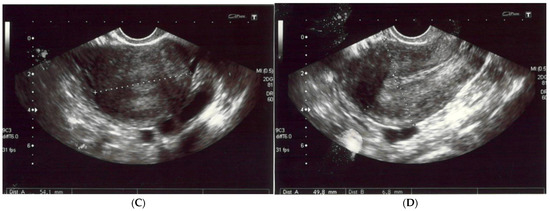

A 56-year-old non-obese, non-smoking female (gravida one, para one) presented with severe diffuse headaches lasting for 2 months, accompanied by retro-orbital pain. She had no history of uterine fibroids according to sonography (Figure 1) nor had she had hormonal treatment after menopause or a hysterectomy. There were no abnormalities found during physical and neurological examinations. There was no pathological resistance nor tumors in the subcutaneous tissue upon palpation. The basic laboratory tests were within the normal ranges. The patient’s anti-HIV tests were negative. She had no history of neoplasm nor recurrent infections and she did not use steroids. There were no medical conditions that indicated immunodeficiency.

Figure 1.

(A,B) The left and right ovaries, with their diameters. The right ovary measured 25 × 15 mm and the left ovary 24 × 14 mm. (C) The transverse plan of the uterus at its widest dimensions. In this plane, the uterine width (Ut-W) was measured. The uterus was of normal size in anterior flexion. (D) The midsagittal plane of the uterus showing the uterine fundus, myometrium, endometrium (6 mm thick), isthmus, cervix and cul-de-sac.